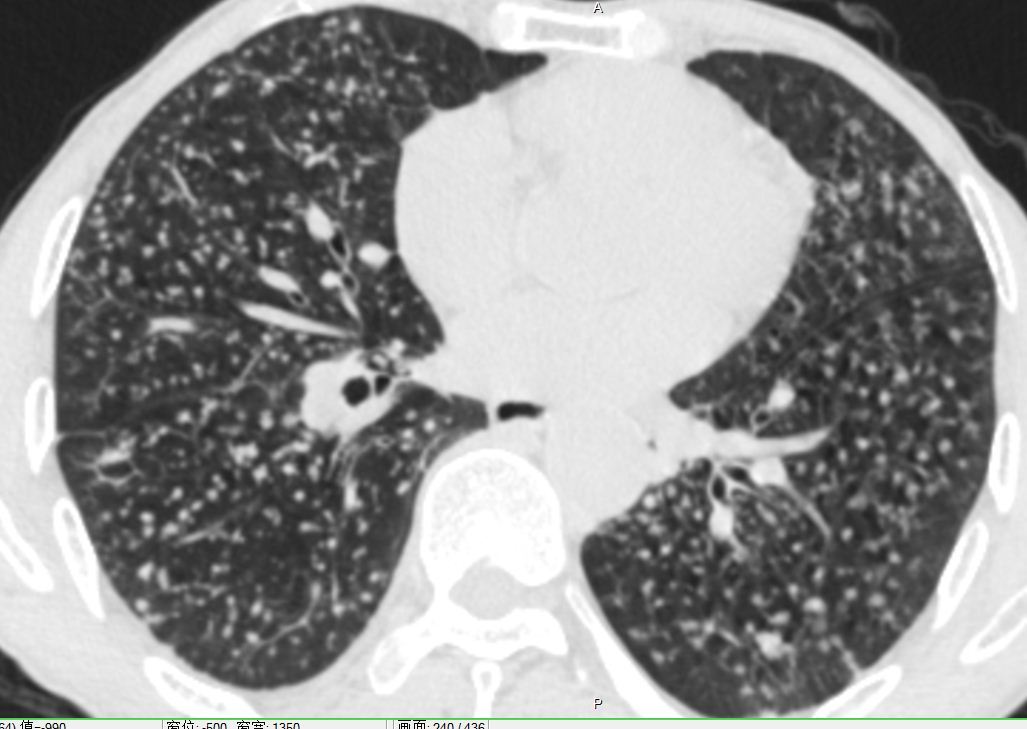

尘肺病

尘肺病人的肺部ct可以看到肺泡内堆积的尘粒 图源:科普中国